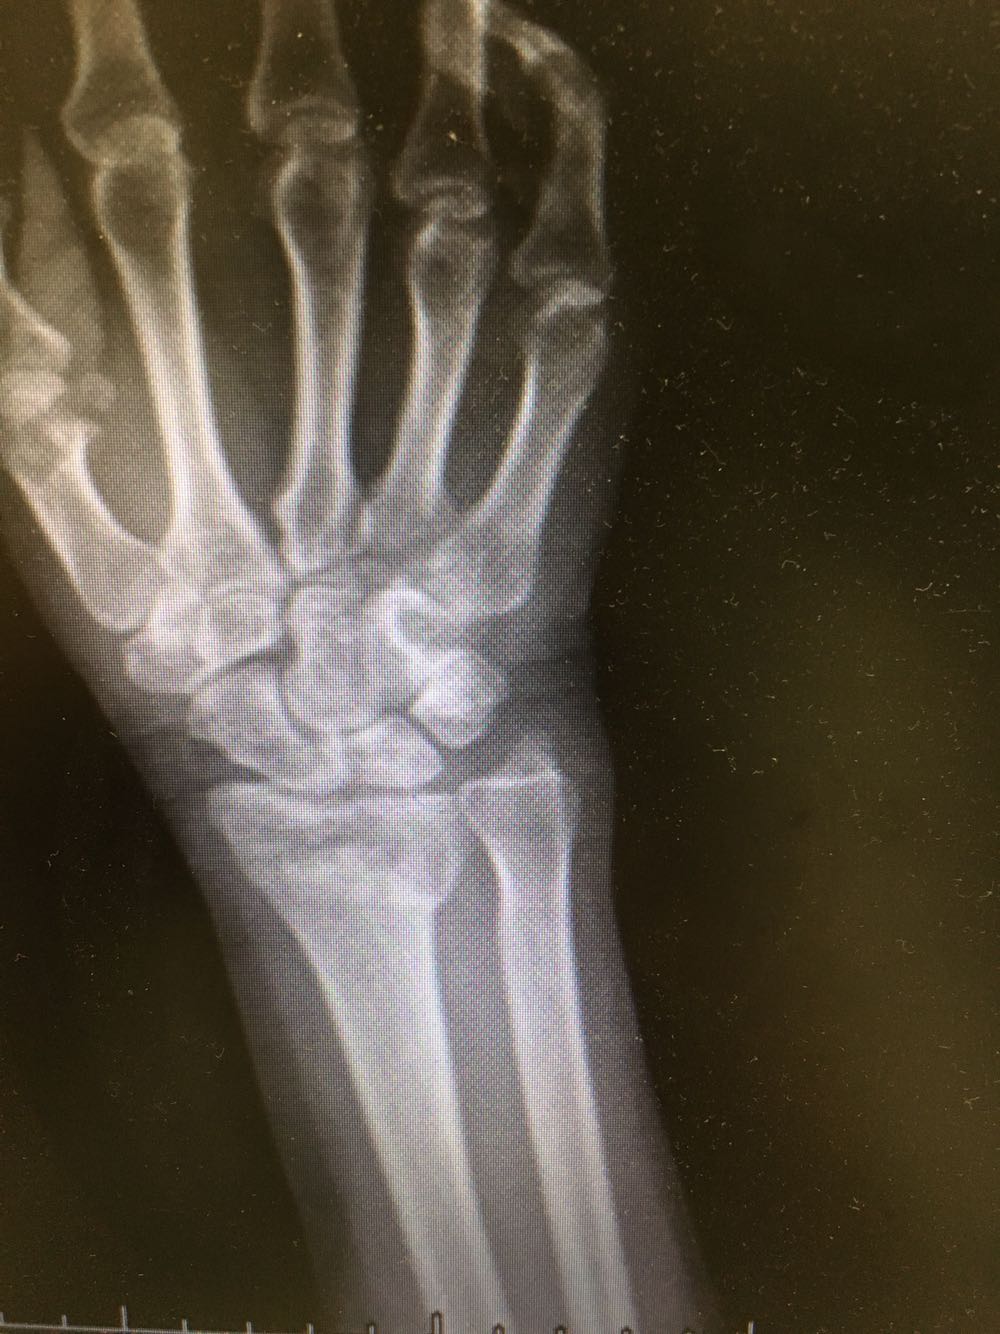

患者,女性,62岁 主诉:外伤致右腕部疼痛伴活动受限8小时 现病史:患者于8小时前受外伤后出现右侧腕部剧烈疼痛,后出现肿胀伴活动障碍,否认头晕头痛、恶心呕吐等不适,遂至我院就诊,查X片示:右侧尺桡骨远端骨折,现为进一步诊治收治入院,发病以来,神清,精神可,胃纳夜眠可,二便无殊,体重无明显变化。

查体:右侧腕部肿胀,压痛阳性,伴活动受限,远端肢体感觉及运动正常。 辅检:见现病史

诊断:右侧尺桡骨远端骨折 治疗:完善术前检查后行手术内固定